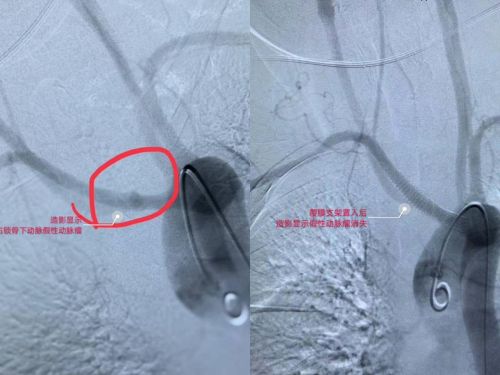

术前ct血管造影可以看到假性动脉瘤形成。

医生为患者施行介入手术成功止血。

术后造影显示,假性动脉瘤消失。

1月24日,刘觉仕主任、龙林副主任医师、孙林副主任医师、蔡煌兴主治医师等为蒋大妈施行迷走右锁骨下动脉(异位开口于降主动脉)假性动脉瘤覆膜支架置入手术。术中,患者再次呕血近2000 毫升,加上入院前出的2000毫升血,几乎相当于全身换血一次。医护人员一边为她输血,一边手术止血,手术历经惊心动魄的近一个小时后终于顺利完成。术后,患者被送入介入血管外科/出血中心监护病房接受后续治疗。